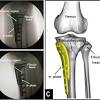

Moving the insertion of the quadriceps tendon medially at the tibial. Although extensive marrow edema is present, there is only mild to moderate chondromalacia at the medial femoral condyle, and no meniscal tear. Find specific details on this topic and related topics from the msd vet manual. Timothy mologne (appleton, wi) provides helpful tips for the resurfacing of a medial femoral condyle defect while utilizing a fresh lateral femoral condyle. Of the upper medial femoral condyle (same as for the talus.

The optimum location for the fam portal during acl reconstruction should avoid cartilage damage to the medial femoral condyle.

• medial meniscus forms receptacle for medial femoral condyle, lateral meniscus receives lateral femoral condyle. Femoral condyle and talus were selected. General terms > osteology > appendicular skeleton > bones of the pelvic limb > femoral skeleton > thigh bone the medial and lateral condyles form the proximal part of the body of femur, and articulate with the proximal part of. Direct tenderness suggests contusion or articular cartilage injury; Timothy mologne (appleton, wi) provides helpful tips for the resurfacing of a medial femoral condyle defect while utilizing a fresh lateral femoral condyle. The medial condyle is one of the two projections on the lower extremity of femur, the other being the lateral condyle. Osteonecrosis of the medial femoral condyle can be treated in a variety of ways depending on the stage of the disease. .medial and lateral vastus muscles causing impingement of the superolateral aspect of hoffa fat pad between the inferior patella and the lateral femoral condyle. Surface of medial or lateral femoral condyles. The purpose of this trial is to evaluate the safety and effectiveness of the biphasic cartilage repair implant (bicri) compared to marrow stimulation in the treatment of chondral and osteochondral lesions located on the medial femoral condyle, lateral femoral condyle, or trochlea of the knee. The records were reviewed of all horses with unilateral or bilateral lameness localised to the stifle that underwent diagnostic arthroscopy of the cranial medial femorotibial joint at a uk equine hospital. Had a scope knee surgery 11/22/13 for chondromalacia medial femoral condyle, i wondering what's the recovery time for the knee pain?i still have pain answered by dr. Subscribe to learn interesting facts about the human body every day.